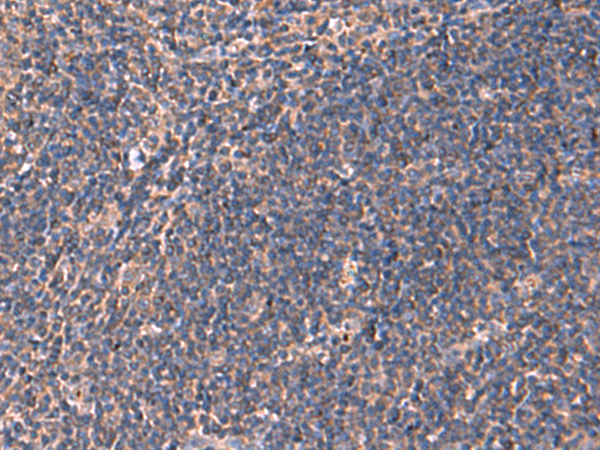

IHC positive control:

Human tonsil and Human cervical cancer

IHC Recommend dilution:

50-300